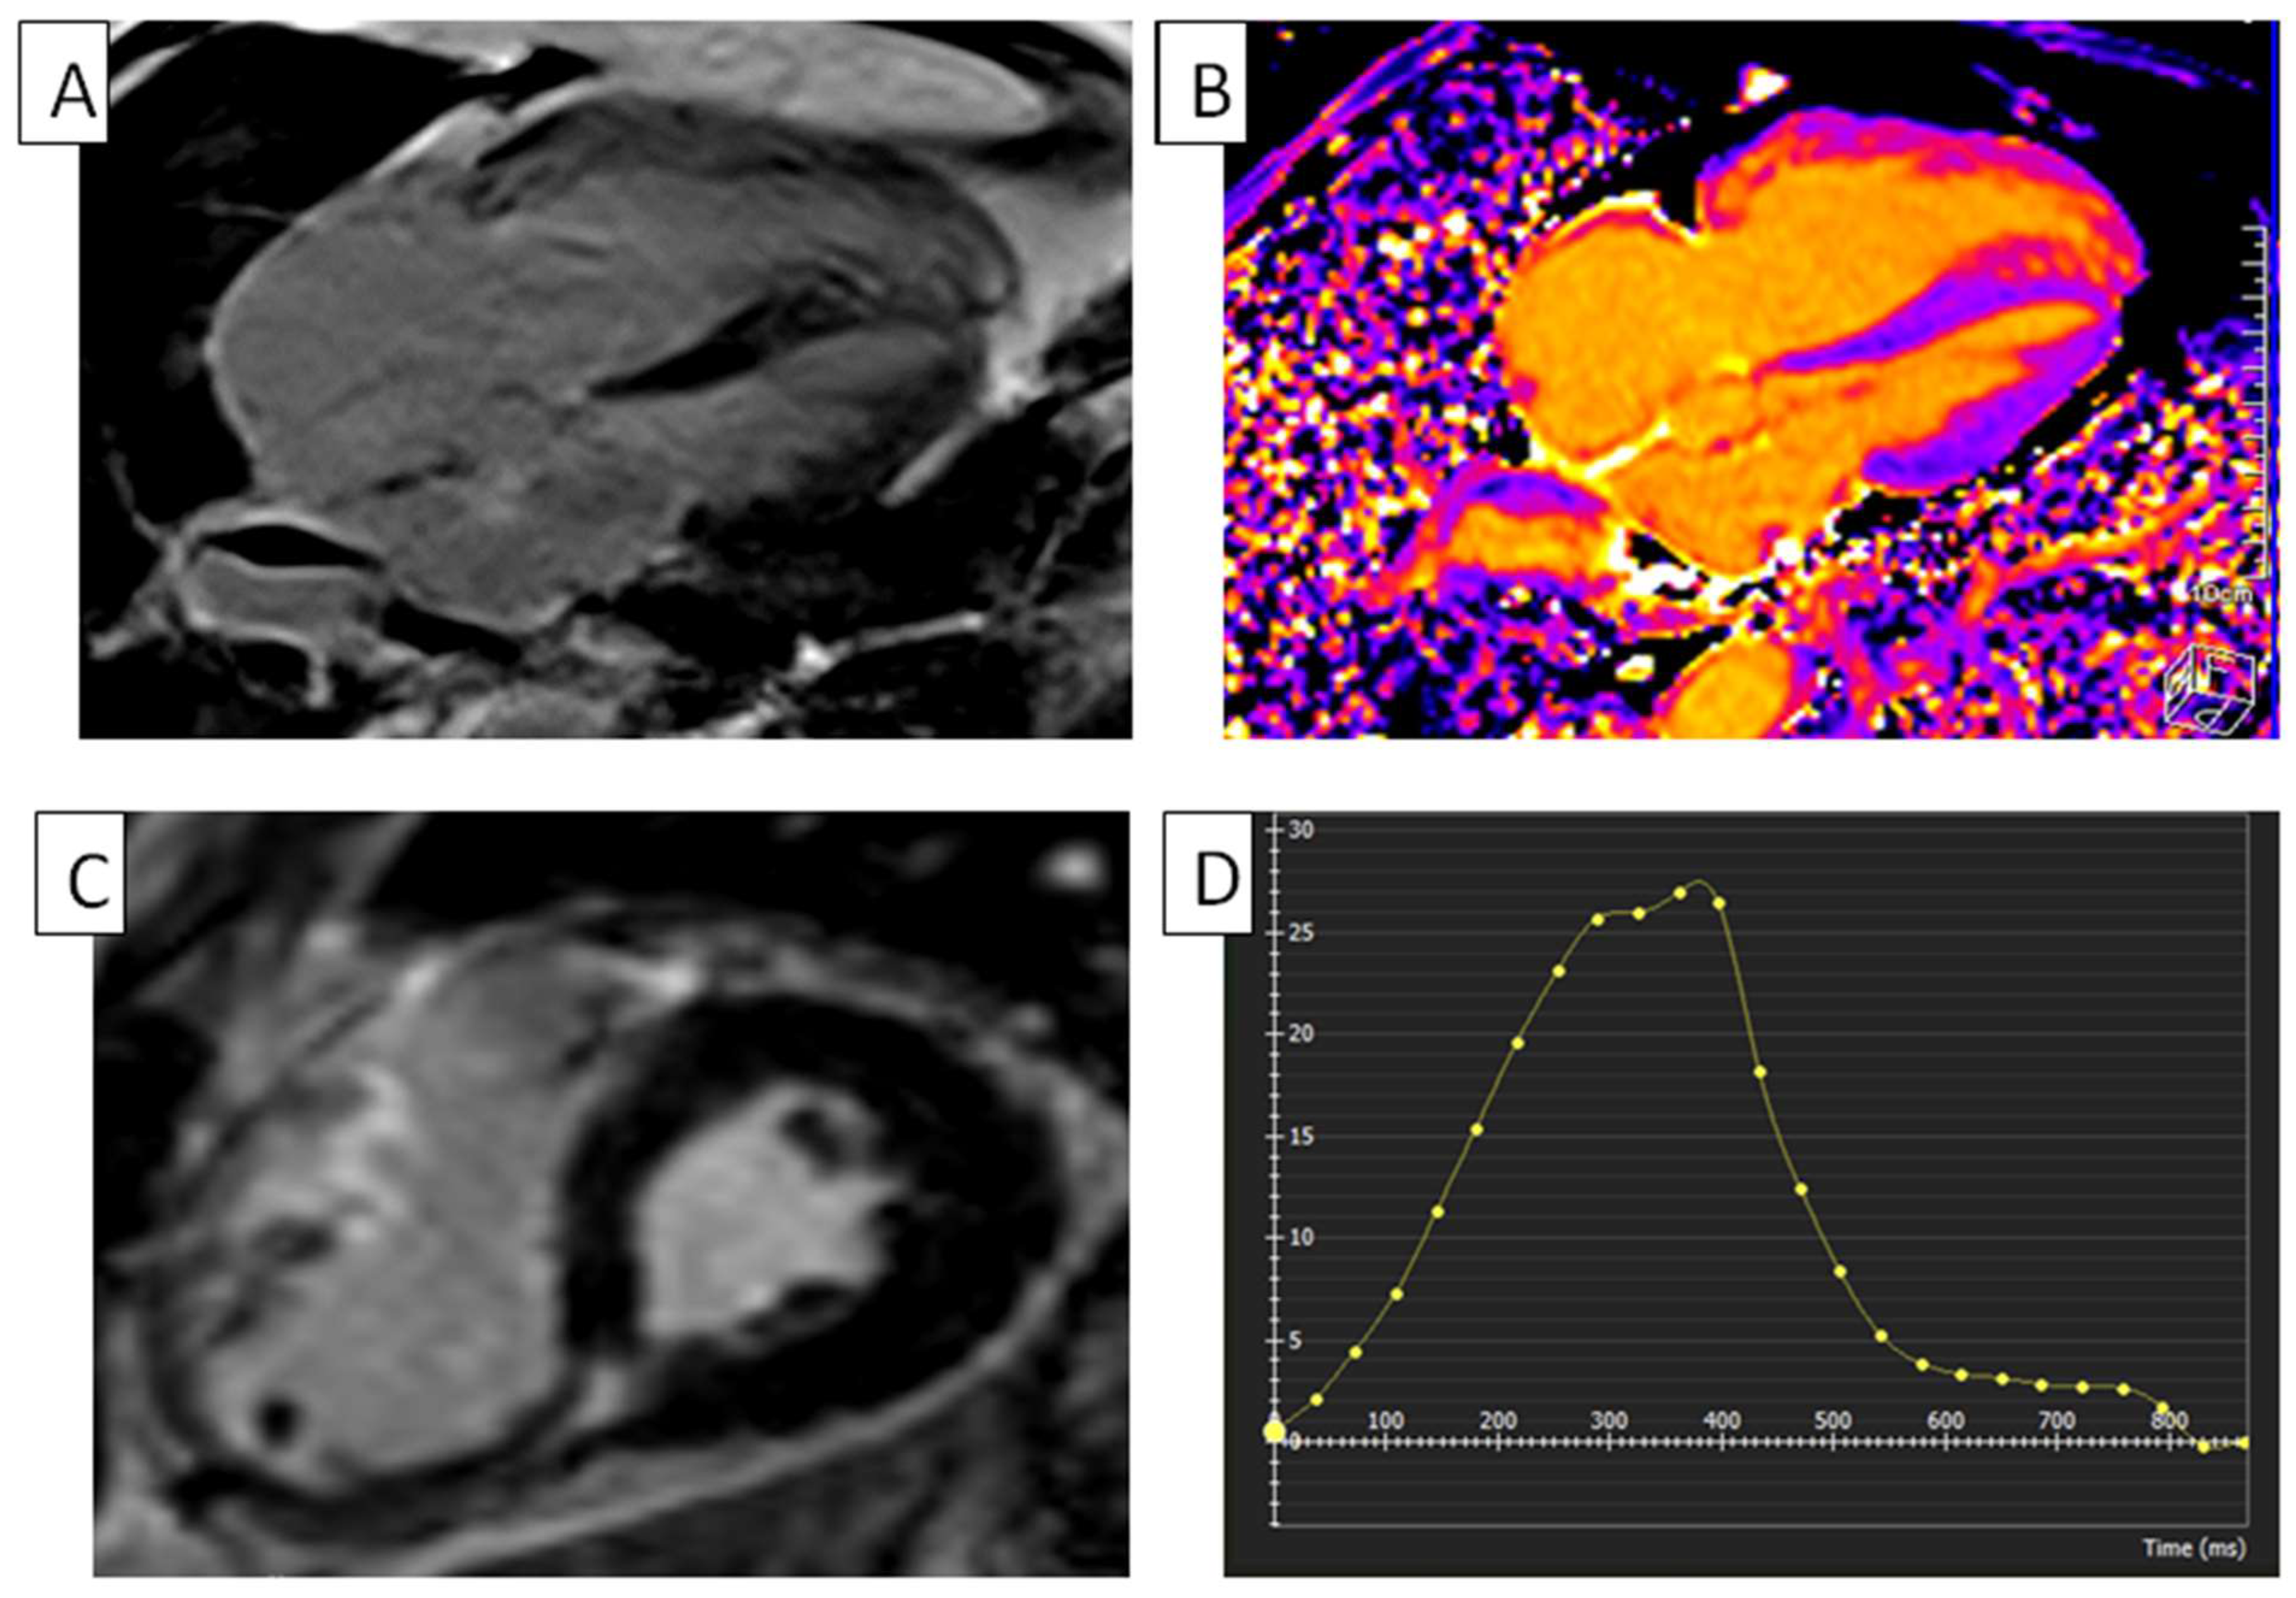

Figure 4.

RV in ARVC. (A) cMRI, with phase-sensitive inversion recovery and four-chamber view, of a patient with ARVC, showing severe dilated and hyper trabecular RV and dilated RA. (B) T1 mapping of a five-chamber view of a patient with ARVC, used to assess myocardial extracellular space, showing severe RV hyper trabeculations and dilatation. (C) Short-axis phase-sensitive in-version recovery cMRI view of a patient with ARVC, showing severe RV dilatation. (D) RV global radial strain in a patient with ARVC. Radial strain values are usually positive. On the graph, the vertical axis shows the radial strain and the horizontal axis shows the time in milliseconds. ARVC, arrhythmogenic right ventricular cardiomyopathy; RA, right atrium; RV, right ventricle; cMRI, cardiac magnetic resonance imaging.